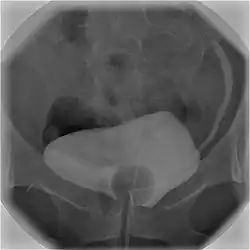

Cystography image showing contrast in the urinary bladder and left ureter (right side of image).

In radiology and urology, a cystography (also known as cystogram) is a procedure used to visualise the urinary bladder.

Using a urinary catheter, radiocontrast is instilled in the bladder, and X-ray imaging is performed. Cystography can be used to evaluate bladder cancer, vesicoureteral reflux, bladder polyps, and hydronephrosis. It requires less radiation than pelvic CT, although it is less sensitive and specific than MRI or CT. In adult cases, the patient is typically instructed to void three times, after which a post voiding image is obtained to see how much urine is left within the bladder (residual urine), which is useful to evaluate bladder contraction dysfunction. A final radiograph of the kidneys after the procedure is finished is performed to evaluate for occult vesicoureteral reflux that was not seen during the procedure itself.[1]